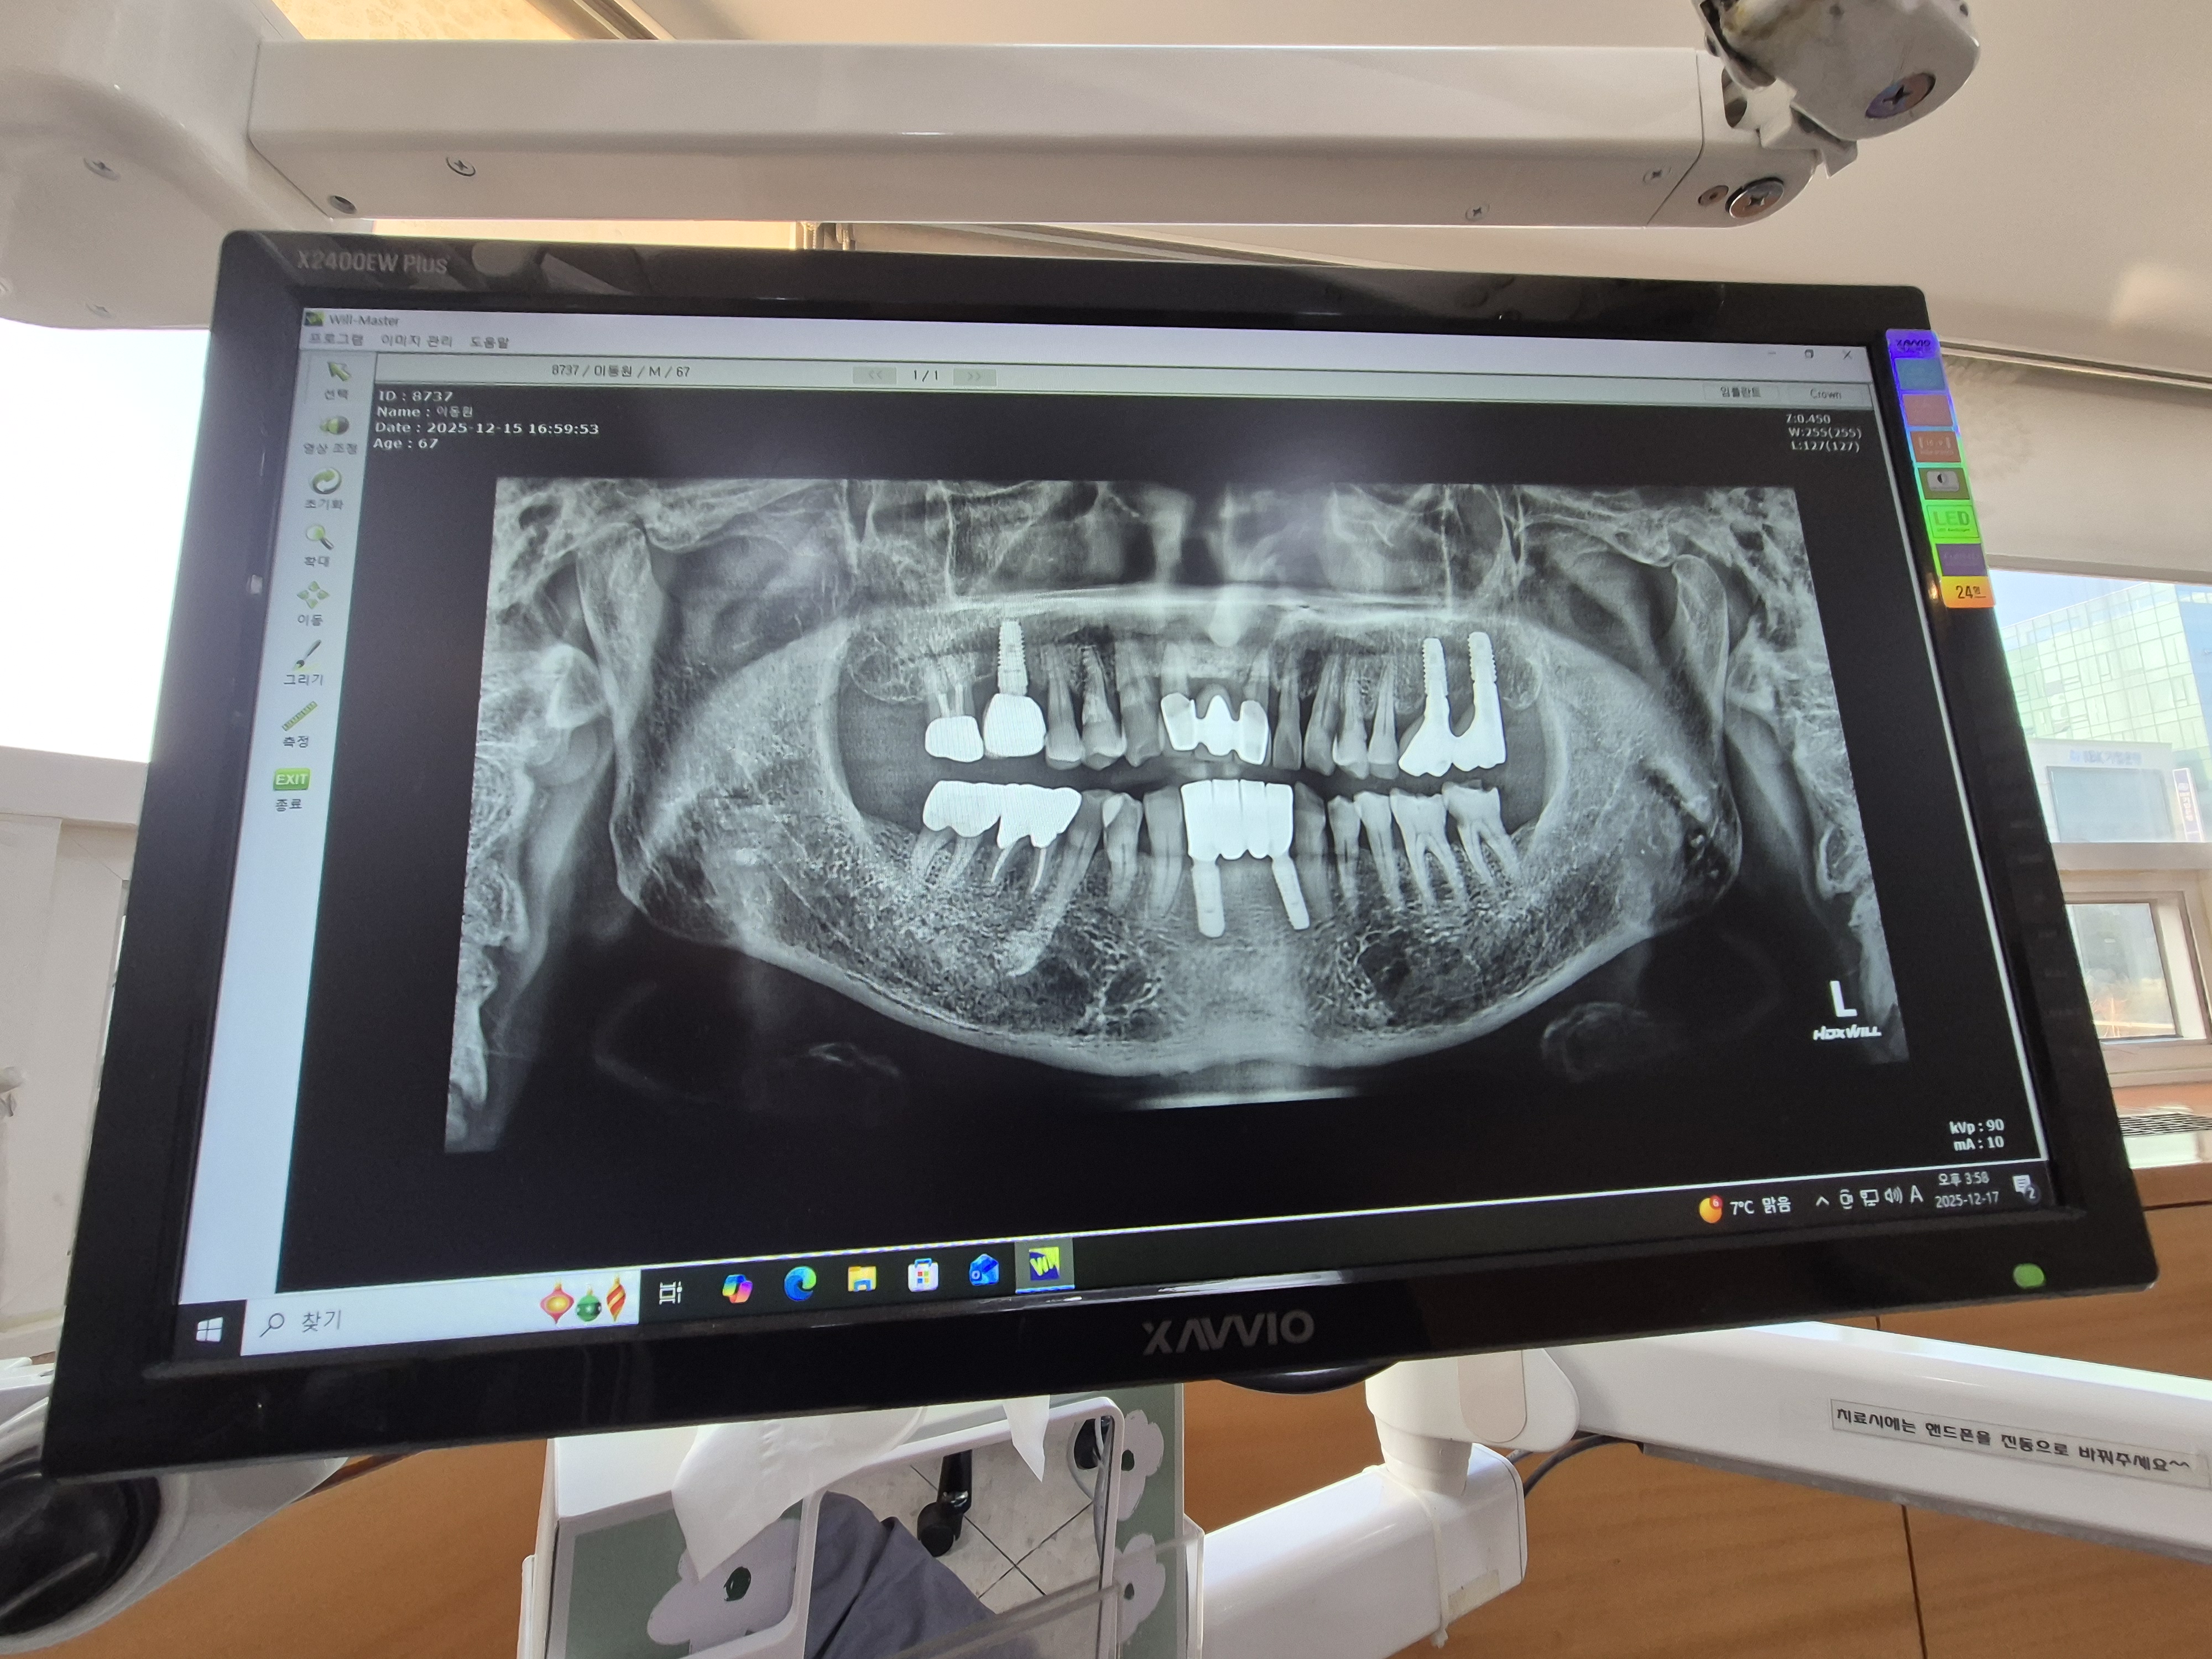

치아사진을 보니 5개의 임플란트와 덧씌우거나 치료받은 이빨이 10개정도.

총체적으로 건강하지못한 치아상태이다.